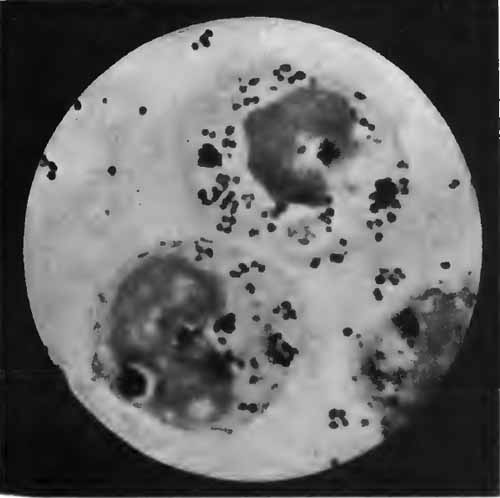

Sputum from a case of actinomycosis

FIG. 8.—Sputum from a case of actinomycosis; stained (Jakob).

5. Actinomyces Bovis (Ray-fungus).—In the sputum of pulmonary actinomycosis and in the pus from actinomycotic lesions elsewhere small, yellowish, "sulphur" granules can be detected with the unaided eye. The fungus can be seen by crushing one of these granules between slide and cover, and examining with a low power. It consists of a network of threads having a more or less radial arrangement, those at the periphery presenting club-shaped extremities (Fig. 8). This organism, also called Streptothrix actinomyces, apparently stands midway between the bacteria and the molds. It stains by Gram's method.

[p. 32] Actinomycosis of the lung is rare. The clinical picture is that of tuberculosis.